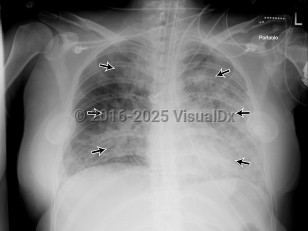

Acute respiratory distress syndrome

Clinically, ARDS is characterized by decreased compliance in the lungs ("stiff lungs"). On a microscopic level, it involves alveolar edema due to increased permeability from membrane destruction ("leaky capillaries") as well as neutrophil infiltration, which can lead to activation of a localized inflammatory response. Once the alveoli are damaged, they will start to collapse, leading to atelectasis derecruitment of the lung. Although mechanical ventilation is the mainstay of treatment, it can be challenging and must be done carefully and within specific parameters, as repetitive re-expansion and collapse of the alveoli can lead to mechanical injury known as atelectrauma and the elevated mean airway pressures or excess tidal volumes in the setting of decreased lung compliance result in alveolar barotrauma / volutrauma.